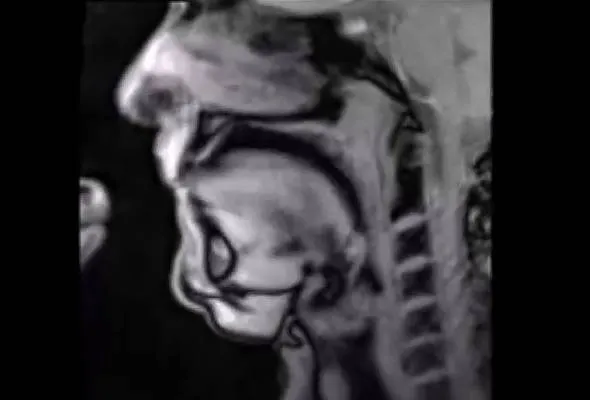

Untuk melihat proses yang berlaku dalam otot vokal individu, ahli biofizik, Jens Frahm dari Institut Biofizik Max Planck telah menggunakan teknik MRI untuk melihat perubahan fizikal yang berlaku kepada tubuh manusia.

Walaupun agak ngeri untuk ditonton, lihat saja keupayaan tindakan fizikal pada lidah, bibir dan bahagian laring yang menjadi asas pembentukan vokal kita.

Ia bekerjasama untuk membentuk ucapan dan suara yang dikeluarkan.

Ini merupakan satu kejayaan baru dalam dunia perubatan di mana sistem ini mampu digunakan untuk meneliti aktiviti tubuh manusia seperti siaran langsung televisyen.

Sistem ini dibangunkan oleh Jens Frahm dari Institut Max PLanck dari Jerman